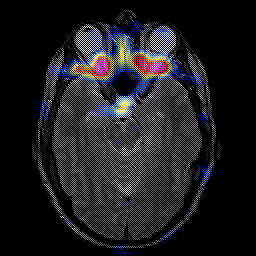

glioma overlay -- Slice #10

[Home][Help][Clinical] Slice 10